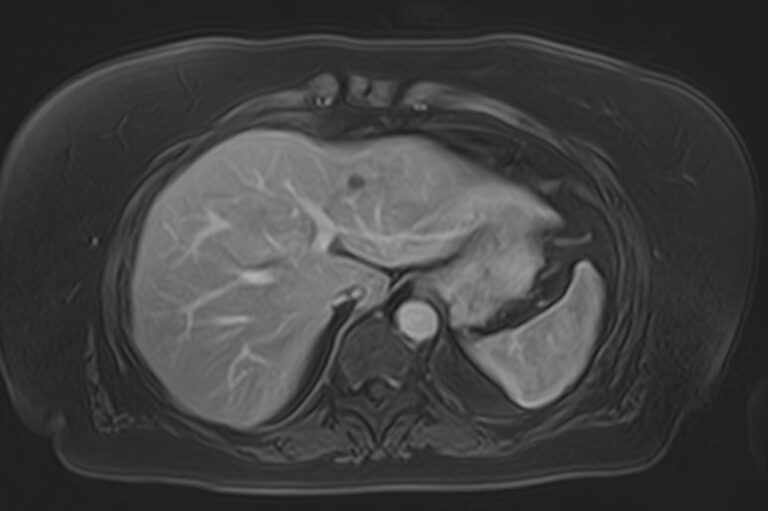

Магнитно-резонансная томография является современным наиболее информативным методом диагностики заболеваний печени. С помощью использования магнитного поля, обладающего высокой индукционной мощностью, МРТ позволяет получать послойные изображения органа и окружающих тканей и выявлять патологические изменения в печени на самых ранних стадиях развития, когда другие методы диагностики не дают результатов.

Для повышения качества визуализации патологических очагов поражения дополнительно применяется контрастное усиление. Для этого в вену вводится контрастный препарат, содержащий гадодиамид (соли металла гадолиния). Контраст позволяет оценить степень и характер васкуляризации в очагах поражения. Методика применяется для ранней диагностики как первичных опухолей печени, так и метастатического поражения, что имеет решающее значение для проведения своевременного лечения.

В клинике «Доступная медицина» исследование проводится на современном высокопольном томографе экспертного класса TOSHIBA VANTAGE TITAN 1,5 Тесла. Аппарат послойно сканирует исследуемую зону в трех плоскостях с шагом от 1 мм, при этом получая данные о структуре органа в мельчайших подробностях. Инновационные компьютерные программы реконструируют данные в трехмерные модели органа, отображающие состояние не только паренхимы печени, но и внутрипеченочных желчных протоков и сосудистой системы.